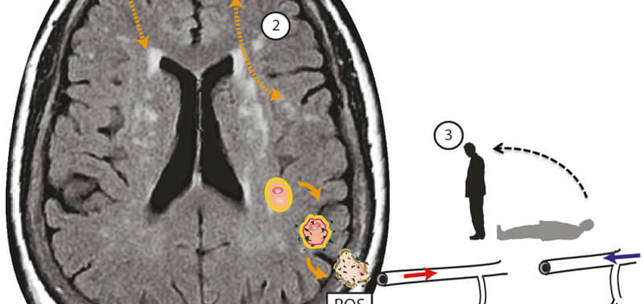

Unexplained dizziness in elderly patients